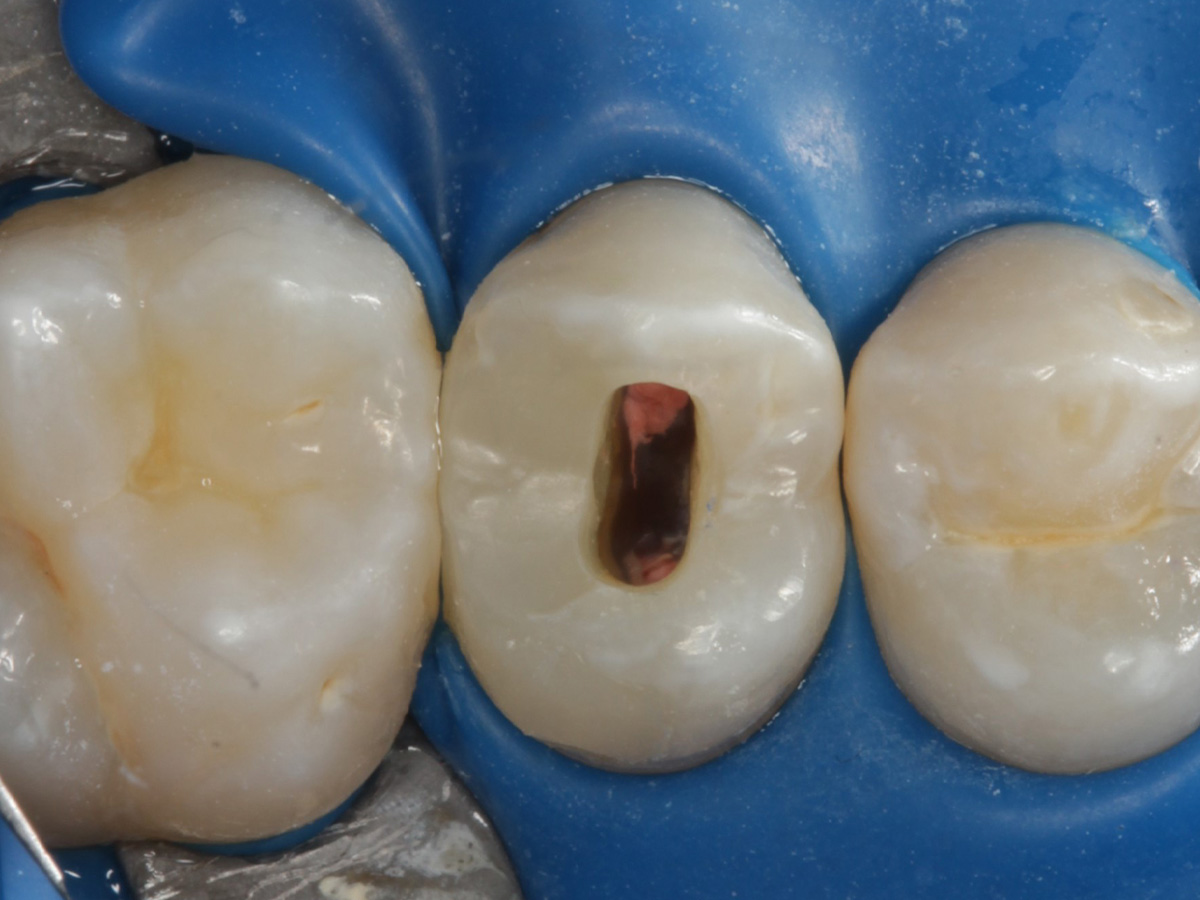

Abbildung 5

Height Indicator vor Auswahl der passenden Evolve Matrize nach Defektdarstellung, Kariesexcavation, Vitalexstirpation

Abbildung 24

Folgesitzung: Trepanation Zahn 25